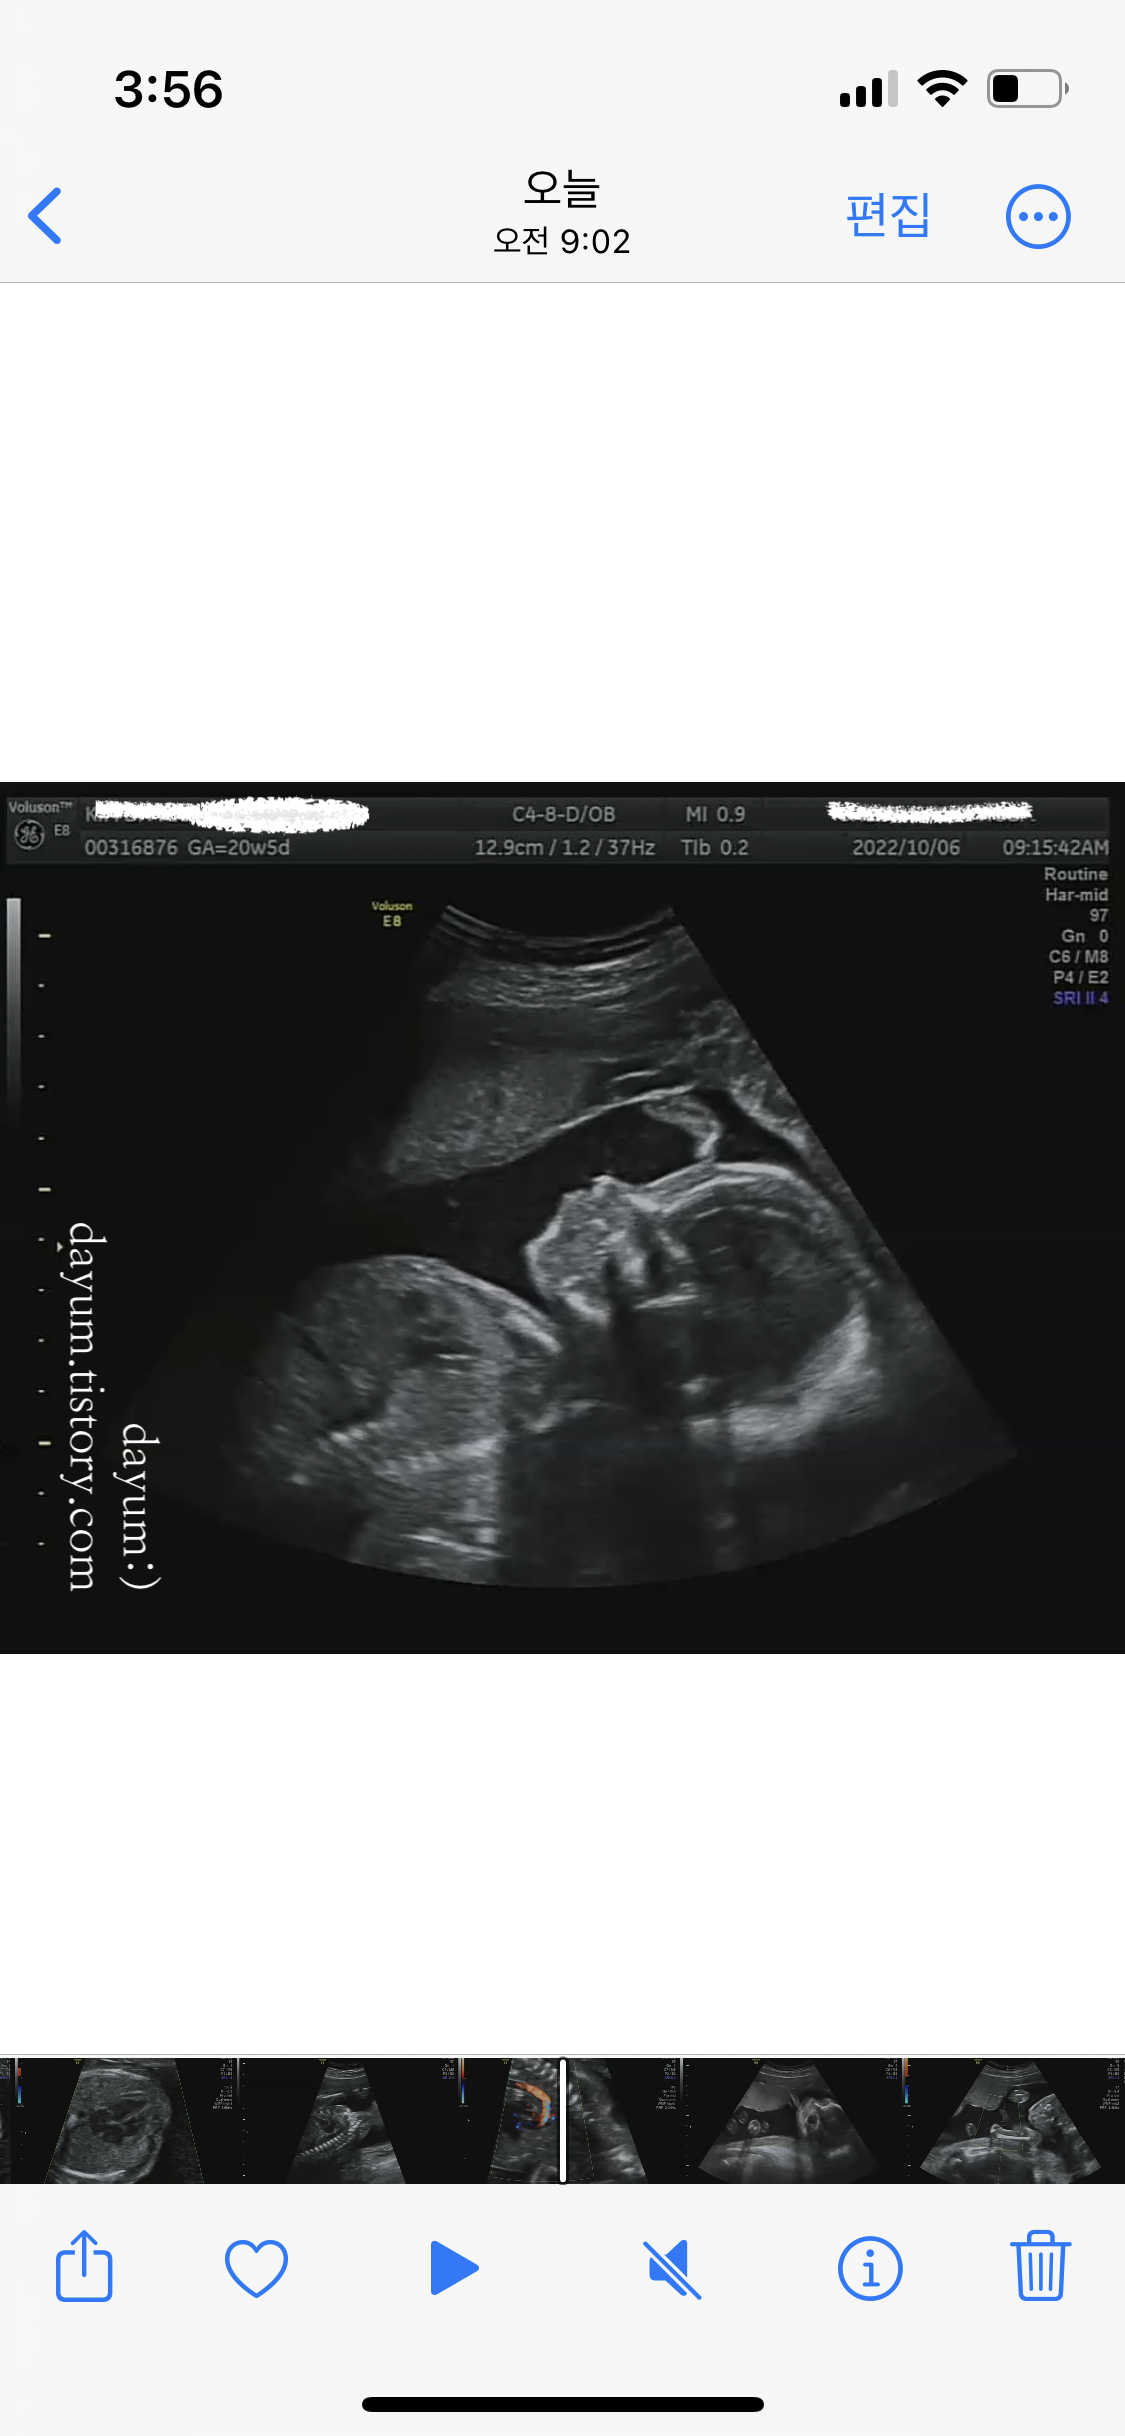

보통 20-30분이면 된다는데 이번에도 조이가 잘 협조해줘서 금방 끝났다.

녹화기록을 보니 11분 정도 녹화되어 있었다. 엄청 빨리 끝난편... 처음에 옆으로 고개를 돌리고 자고 있어서 얼굴을 잘 안보여주다가 마지막에 자다가 깨서 얼굴도 봤다.

초음파선생님이 머리둘레부터 언청이 확인, 뇌모양, 손가락, 발가락, 배둘레, 심장, 위 등 생성된 장기들을 설명해주시고, 탯줄에 혈액이 잘 들어가는지, 자궁은 괜찮은지, 양수의 양과 경부길이까지 싹다 훑어주셨다.

조이는 모두 정상범위로 잘 자라고 있고, 초음파상 정상이라고 한다.